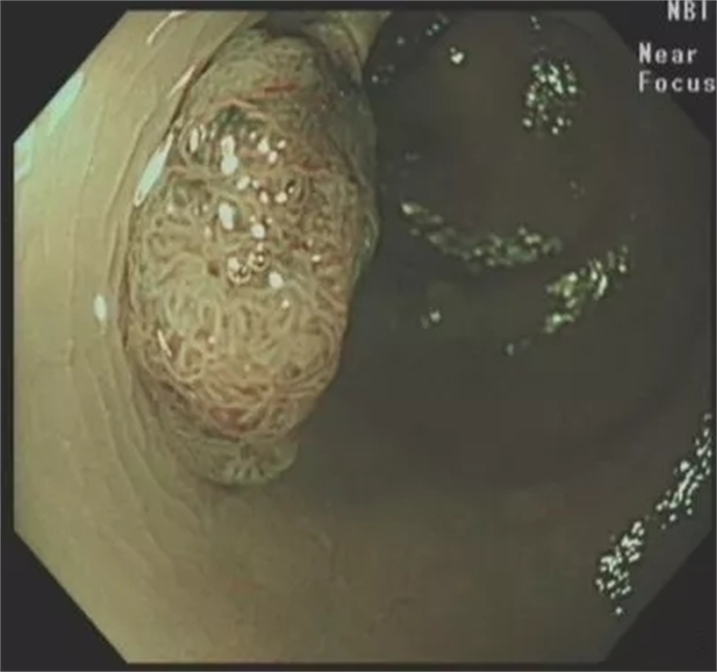

NBI仔细观察发现局部腺管排列紊乱,考虑局灶高级别病变。